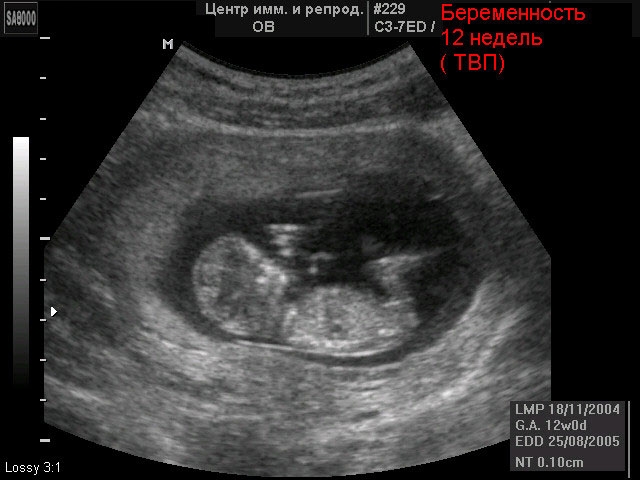

Pendant une échographie, vous pouvez clairement voir à quoi ressemble le fœtus. Déjà sans décodage et explication du médecin, on peut distinguer les contours du corps. Le corps du bébé est légèrement plus grand que sa tête, et les bras et les jambes sont à peine reconnaissables - ils sont toujours très courts et minces. Dans de très rares cas, un équipement moderne permettra au médecin de reconnaître le sexe de l'enfant - à condition que l'entrejambe du bébé soit clairement visible. Sur les diagnosticiens standard, ces informations ne seront pas disponibles pendant longtemps.

Si vous n'êtes pas inscrit, consultez le médecin. Pour une période de 11 à 13 semaines, il est temps de procéder à ce que l'on appelle un dépistage. Il s'agit d'un examen complet. À l'échographie, le médecin vérifiera certains paramètres spécifiques du fœtus. Par exemple, il évaluera la taille de la région occipitale, selon laquelle la menace du syndrome de Down est déterminée aux premiers stades. Des analyses de sang pour certaines hormones révèlent, le cas échéant, diverses malformations du fœtus.

Habituellement, la première échographie à 12 semaines est effectuée. J'ai remarqué que le sexe des filles ne parle jamais à ce moment, carrien n'est encore visible. Mais, qui a des garçons, leur ont-ils dit lors de la première échographie.)))